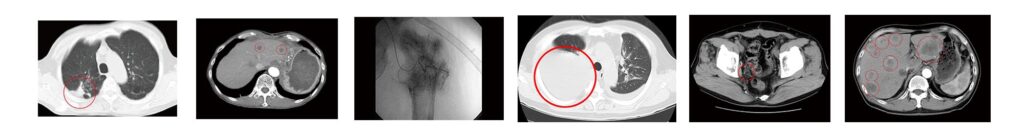

17) すい臓がん症例①②③④⑤⑥

(※)エビデンス 治療担当・院長:宇野克明の研究/臨床実績。がん免疫治療の研究/臨床応用(外来診療)開始以来、およそ29,000例の治療経験症例を有しています。1997年10月24日〜2023年10月31日。